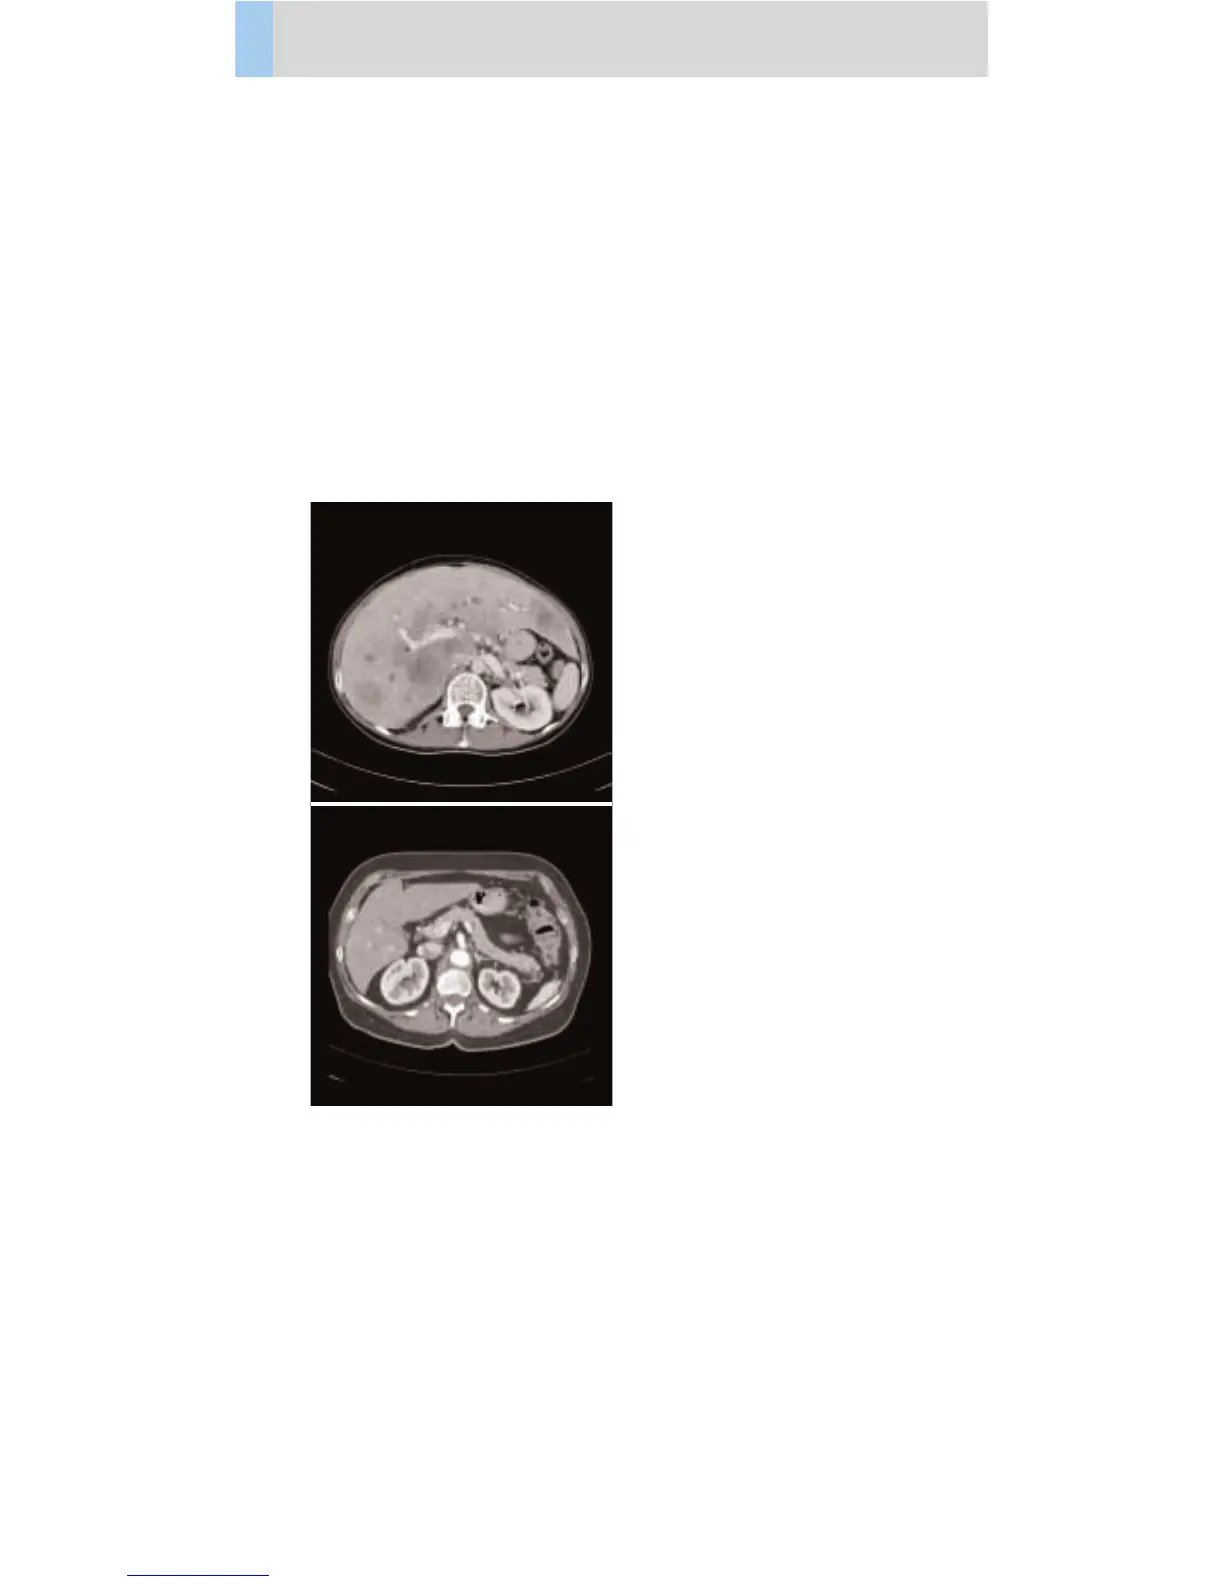

Abdomen

AbdRoutine06s

Spiral mode for all routine studies in the region of

abdomen, e. g. screening, follow-up examinations

etc., using a 0.6 sec. rotation time.

A complete abdomen scan in a range of 20 cm will be

covered in 9.2 sec.